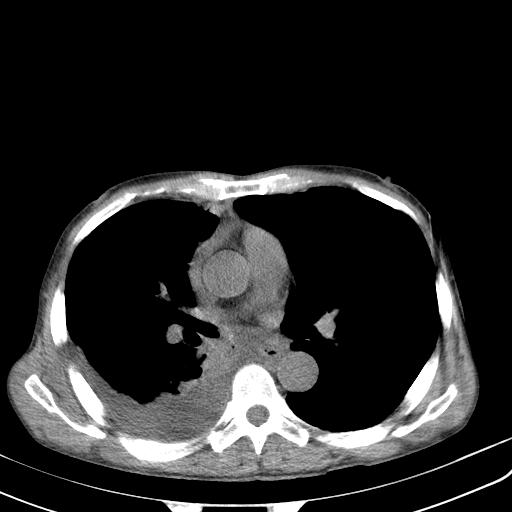

男性 75  咳嗽 一周前发热最高达39

右肺继发型tb并右侧tb性胸腔炎,右侧胸腔大量积液并右下肺膨胀不全,慢支肺气肿、多发肺大泡。建议抽胸水实验室检查并复查排除恶性在占位。

右上肺继发型肺结核,右胸腔中等量积液。

结核的基础上有纵隔淋巴结肿大,右侧有胸水,但右侧纵隔反而窄,说明有肺有不张。

再就是右下肺有块影,和不张混合,还是不能除外肺癌。

补充材料,患者2月份ct片大致正常,双侧胸腔积液,2月份抽胸水未发现ca细胞,现患者发热,痰多,各气管通畅,

1)右肺继发型肺结核。2)左肺胸膜下多发性肺大泡。3)右侧胸腔积液。